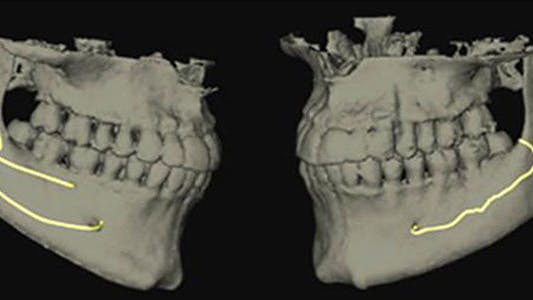

No. 2: Violations of a branch of a bifid or trifid mandibular canal

The IAC is typically described as a singular canal4 containing the neurovascular bundle that clinicians know not to violate, and a 2 mm “safety zone”5 has been described when placing dental implants. It is now known that multiple smaller branches of the IAC can occur that run parallel to the main trunk of the canal.6 Up to 40% of the nerve can branch off the main canal, and if these branches are large enough, a secondary or even tertiary canal can result (figure 2).

Multiple branches of the mandibular canal often go unrecognized, because many dentists are unaware of this anatomic variation even though the canals may be visible on a panoramic radiograph or CT scan. Violations of this secondary/tertiary canal resulting in pain post-implant placement have been described in the literature.7